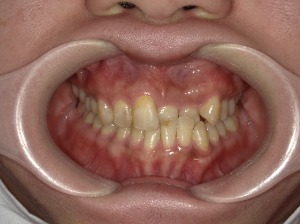

治療前

治療中

治療後